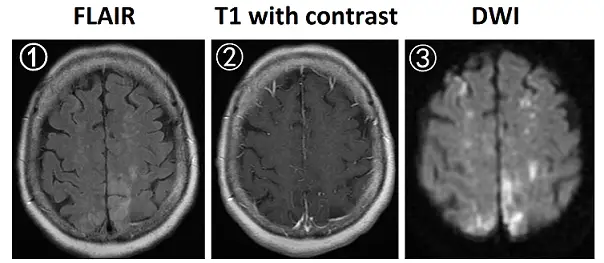

70歲女性為肺癌病人,因右腳無力就診,抽血檢查發現D-dimer檢驗數值為16 mg/L(正常值為<0.5mg/L),腦部磁振造影(MRI)檢查結果如下圖(①fluid–attenuated inversion recovery [FLAIR];②施打顯影劑之T1影像;③diffusion–weighted imaging [DWI])。下列何者最可能是腦部病灶的原因?

從FLAIR影像(圖①)可見雙側頂葉及中央溝附近皮質下出現多發不對稱高訊號區,呈現水腫樣改變。T1加強影像(圖②)上述高訊號區並未出現實質性或環狀強化,缺乏腫瘤或膿瘍常見之血腦障壁破壞後未增強表現。DWI影像(圖③)對應區域均呈現明顯高訊號,符合彌散受限,代表細胞性水腫,與急性梗塞一致,非單純血管外滲性水腫(即vasogenic edema) (pubmed.ncbi.nlm.nih.gov)。